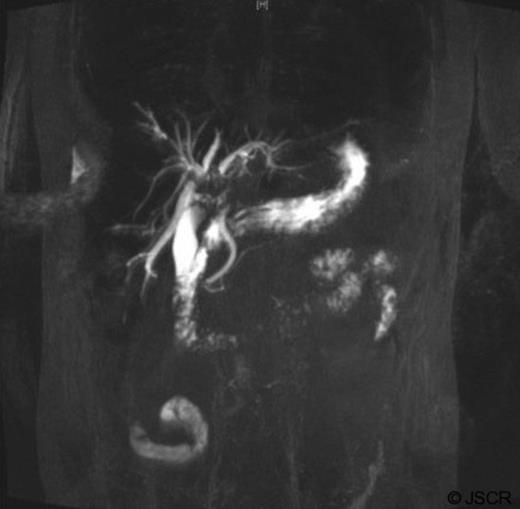

The mass had mild hyperintense signal on T2-weighted images and capsule retraction, suggesting a scirrhous lesion (figure 3); possibly cholangiocarcinoma.

T2 weighted abdominal MRI, coronal view displaying right lobe liver mass.